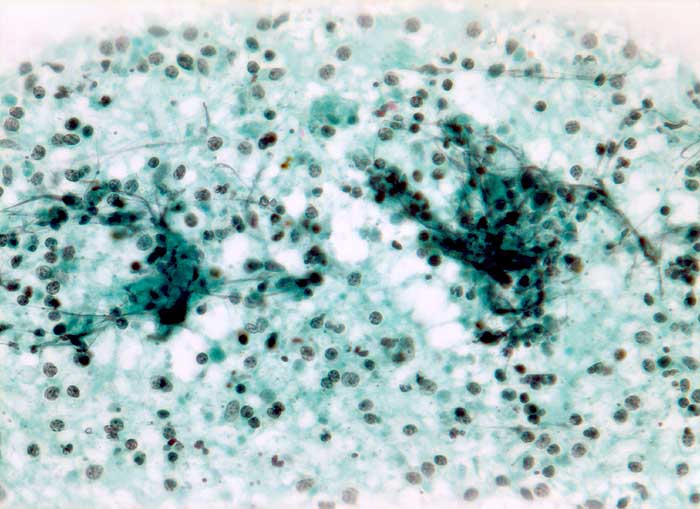

Tuberkulöse Lymphadenitis

Entzündung infektiös

Die meist atrophischen Epitheloidzellen sind oft nur schwer von Venulenendothelien unterscheidbar und sind nur relativ selten zu deutlich erkennbaren Granulomen zusammengeballt. Bei Vorliegen von verkäsenden Granulomen erscheint der Ausstrich feinkörnig-detritisch. Eine granulozytäre Entzündung muss bei AIDS Patienten an eine Tuberkulose denken lassen.

Die Ziehl-Neelsen Färbung zum Nachweis der säurefesten Stäbchen kann nachträglich am Pap-gefärbten Präparat durchgeführt werden.